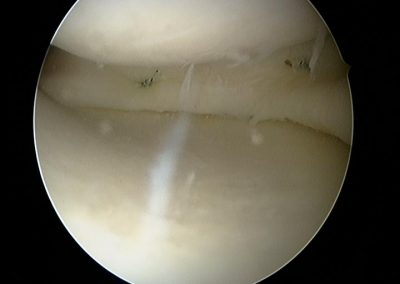

Photos intra-articulaires d’une réparation méniscale arthroscopique